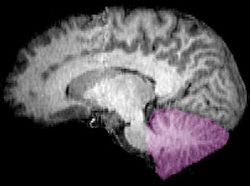

المخيخ Cerebellum هو القسم الكروي الأصغر الذي يقع أسفل نصفي الكرة المخيتين في الدماغ ، يهتم المخيخ بشكل أساسي بوظائف التوازن و تنظيم الوظائف الحركية. يقع أسفل النصفين الكرويين في الجهة الخلفية للمخ ويتركب من فصين أيمن وأيسر يصل بينهما فص ثالث.

cerebellum (Latin for "little brain") is a major feature of the hindbrain of all vertebrates. Although usually smaller than the cerebrum, in some animals such as the mormyrid fishes it may be as large as or even larger.[1] In humans, the cerebellum plays an important role in motor control. It may also be involved in some cognitive functions such as attention and language as well as emotional control such as regulating fear and pleasure responses,[2][3] but its movement-related functions are the most solidly established. The human cerebellum does not initiate movement, but contributes to coordination, precision, and accurate timing: it receives input from sensory systems of the spinal cord and from other parts of the brain, and integrates these inputs to fine-tune motor activity.[4] Cerebellar damage produces disorders in fine movement, equilibrium, posture, and motor learning in humans.[4]